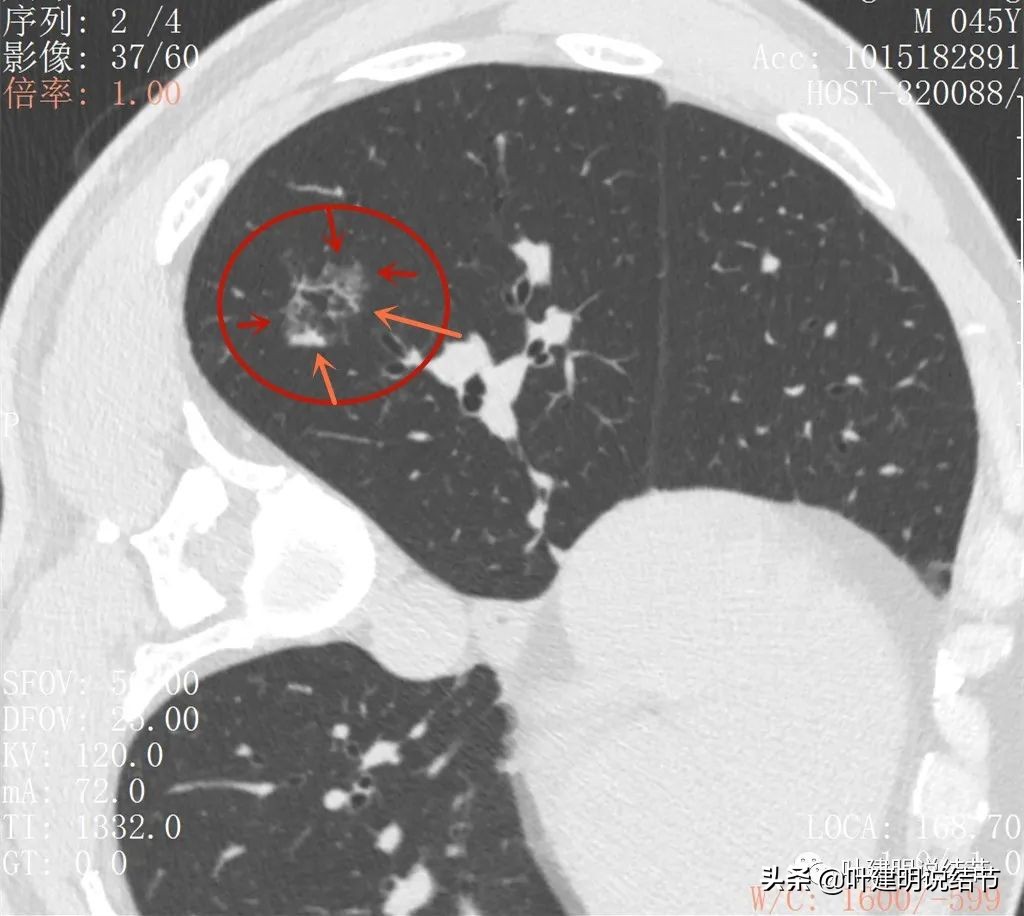

丽水的某A,今年45岁,男性。几个月前检查发现右肺下叶磨玻璃病灶,在当地医院检出后,某市医院胸外科专家看过后考虑恶性可能性大,建议其手术。但他听朋友介绍于2022年2月份来我门诊就诊,予以查了胸部CT平扫加右下叶靶扫描。我们先来看他当时的影像:

2022年2月平扫:

右下叶淡而散在的磨玻璃影

整体轮廓有点清楚,似见血管走行于病灶处

密度略不均